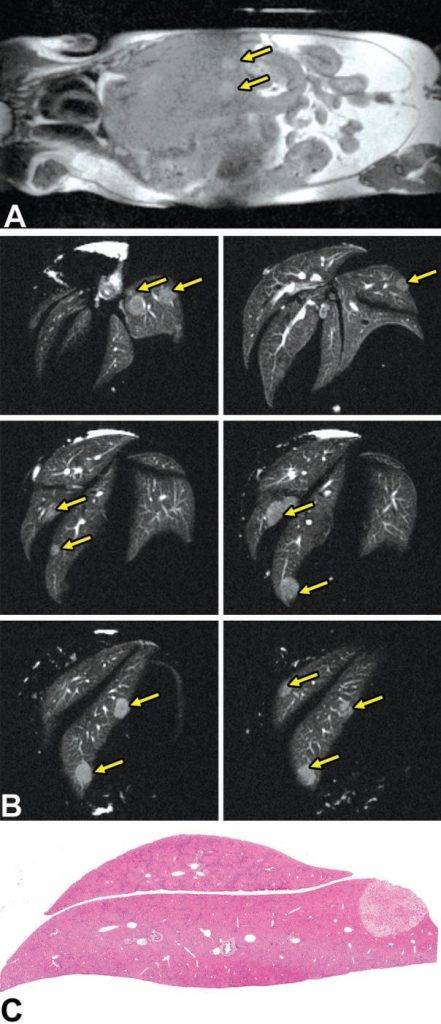

活體磁共振成像在模型小鼠中檢測(cè)到局灶性肝損傷(圖A)。肝臟的高分辨率離體MRH評(píng)估可以在小鼠(圖B和C)中鑒定幾個(gè)單獨(dú)的局灶性脂肪病變。通過(guò)常規(guī)組織病理學(xué)證實(shí)病變?yōu)榫衷钚灾靖淖儯▓DC)。